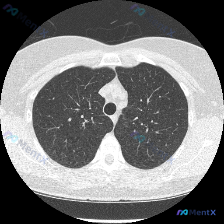

网上看到一份胸部CT肺窗读片资料,影像核心表现是:双肺弥漫分布大量粟粒状及小结节状影,大小比较均匀、密度一致,全肺弥漫随机分布,没有明显胸膜下聚集或支气管血管束周围分布偏好,没有钙化、空洞,也没有胸腔积液或胸膜增厚。 这份影像的表现非常典型,想问问大家,只看目前这些影像资料,你们第一眼会先考虑哪个方...

整理了一份胸部CT病例,影像结果明确:双肺弥漫性随机分布粟粒样结节,存在肺空域混浊,已知信息提示患者无发热。 按照这份信息,大家第一眼会把哪个诊断放在第一位?诊断思路会从哪里切入?

看到一份很有训练价值的读片病例,整理了完整的分析思路分享给大家。 病例影像基础信息 这是一张心室水平的胸部CT横断面肺窗图像,图像质量良好,伪影少,窗宽窗位合适,能清晰显示肺实质结构: - 胸廓形态规则,纵隔居中,双侧肺野基本对称 - 双侧胸膜光滑,无增厚、积液或钙化,所示胸壁骨质未见明确异常 -...

最近看到一份胸部CT肺窗的影像资料,整理了一下思路,和大家分享。 病例信息: - 图像质量:清晰,无明显伪影,呼吸运动影响小 - 解剖层面:胸部下肺野及心室水平,可见心脏、胸椎、肋骨、肺实质等结构 核心发现: - 双肺广泛散在粟粒样结节影,随机分布 - 结节呈点状高密度影,边缘较清晰 - 未见融合、...

整理了一份胸部CT读片讨论,目前只有影像分析结果,没有额外临床资料: 影像核心表现:胸部中下肺野层面可见双肺弥漫散在分布微小结节,密度较高、边界尚清,呈随机性分布,符合血源性播散模式,没有明显大片实变、网格影、胸腔积液。原问题问是否存在"Airspace opacity(气腔混浊)",实际影像核心异...